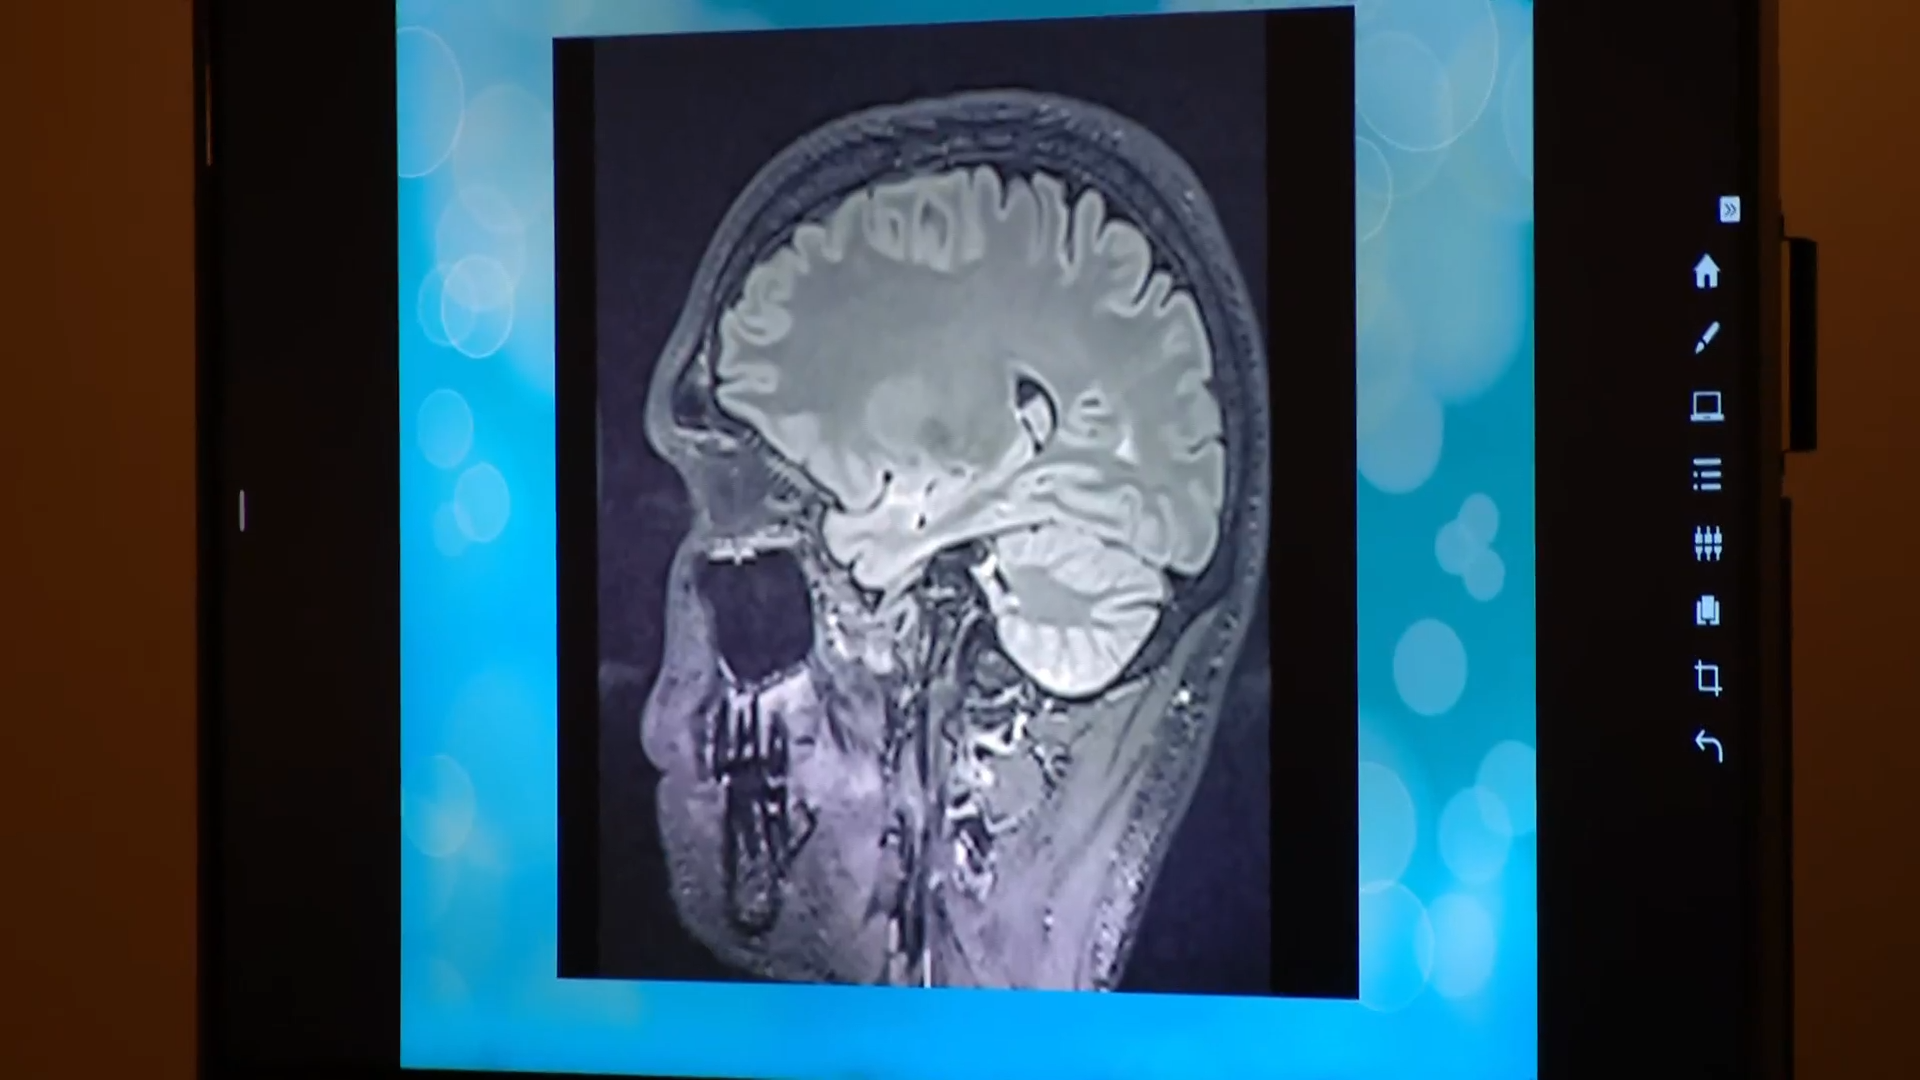

MRI images of Horner’s brain shown in court

Dr. Lewine told the jury that he conducted an MRI scan of Tanner Horner’s brain and showed the jury images from that scan.

According to Lewine, the volumetrics from Horner’s scans show that “things are mostly within normal [range], but there is one particular area that is abnormally low.”

Lewine said that Horner’s left orbitofrontal area was 20% lower than the average person’s, meaning that he had approximately 50 million fewer neurons.

“The left orbitofrontal cortex is one of these key brain regions involved in the emotional regulation of behavior and social cognition,” Lewine said. “It is often disrupted in autism spectrum disorders. And again, that’s based on the scientific literature. It can be disrupted and traumatic brain injury. It can also be disrupted in depression.”